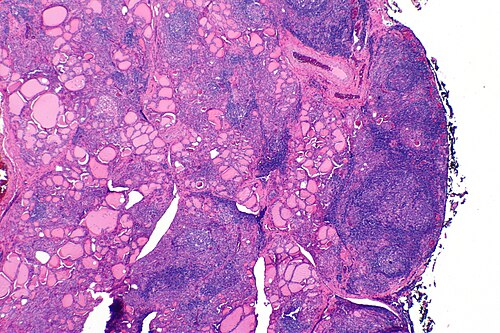

Hashimoto thyroiditis

Librepath · CC BY-SA 3.0 · source

Hashimoto thyroiditis is an autoimmune thyroid disorder characterized by lymphocytic infiltration and gradual destruction of the thyroid gland, leading to hypothyroidism in many patients. First described in the early 20th century, it is associated with autoantibodies and has clinical overlaps with other autoimmune diseases and endocrine disorders. The condition is managed clinically through endocrine assessment, biochemical monitoring, and lifelong hormone replacement when indicated.

Immunopathogenesis has been elucidated through work at immunology laboratories at Pasteur Institute, Max Planck Institute for Immunobiology, Scripps Research, and Howard Hughes Medical Institute investigators, highlighting autoreactive B cell and T cell responses. Antithyroid peroxidase and antithyroglobulin autoantibodies were characterized in serological studies from Yale School of Medicine and University of California, San Francisco. Molecular imaging and histology from pathology departments at Mayo Clinic and University College London demonstrate lymphoid follicle formation, germinal centers, and fibrosis akin to findings in autoimmune disorders studied at National Institute of Allergy and Infectious Diseases and Institut Pasteur. Genetic susceptibility loci mapped in genome-wide association studies by groups at Broad Institute and Wellcome Trust Sanger Institute implicate immune-regulatory genes also reported in research from Stanford University and Harvard Medical School.